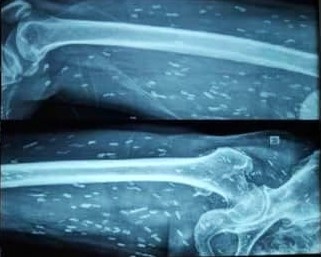

Hình ảnh sán xuất hiện khắp cơ thể người bệnh. Ảnh: BVCC.